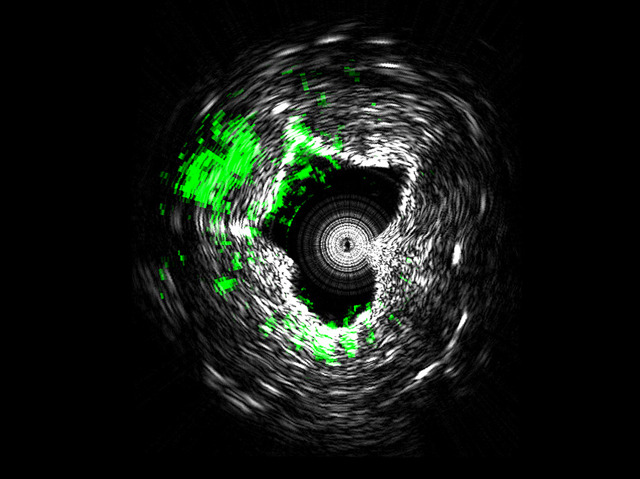

Just as knowing your enemy gives you an edge, advances in medical imaging are allowing scientists and doctors to see more clearly into the development of disease, and so respond more effectively. One particular ambition is to detect the build-up of fatty plaques along the walls of arteries, so as to improve the prevention and treatment of cardiovascular disease. Fat molecules, or lipids, can be identified using ultrasound signals that pick out specific chemical bonds. Combining this technology with a fast-pulsing laser has recently enabled researchers to generate highly accurate three-dimensional images from within blood vessels: pictured is a cross-section of an artery, with lipid deposits highlighted in green. In addition, beyond the image itself, the technique provides information about the nature of the plaque, and how likely it is to rupture and cause disease, making it a potentially powerful diagnostic tool for patients at risk of cardiovascular disease.